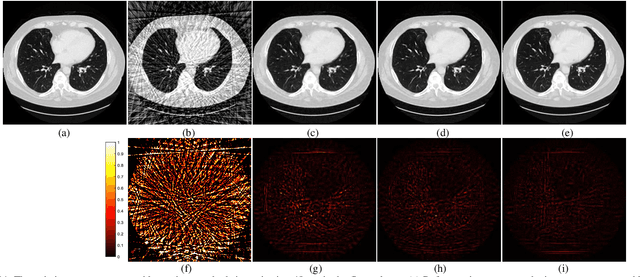

Abstract:Ill-posed inverse problems in imaging remain an active research topic in several decades, with new approaches constantly emerging. Recognizing that the popular dictionary learning and convolutional sparse coding are both essentially modeling the high-frequency component of an image, which convey most of the semantic information such as texture details, in this work we propose a novel multi-profile high-frequency transform-guided denoising autoencoder as prior (HF-DAEP). To achieve this goal, we first extract a set of multi-profile high-frequency components via a specific transformation and add the artificial Gaussian noise to these high-frequency components as training samples. Then, as the high-frequency prior information is learned, we incorporate it into classical iterative reconstruction process by proximal gradient descent technique. Preliminary results on highly under-sampled magnetic resonance imaging and sparse-view computed tomography reconstruction demonstrate that the proposed method can efficiently reconstruct feature details and present advantages over state-of-the-arts.